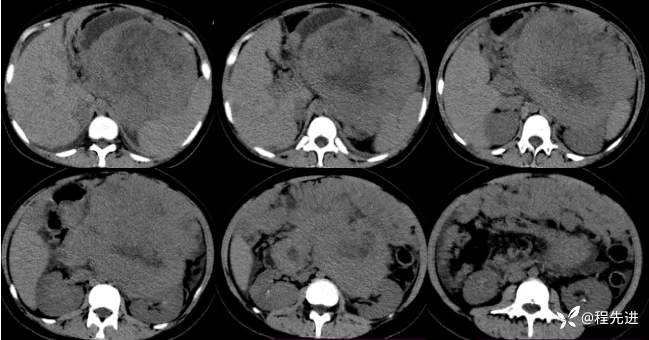

CT平扫: